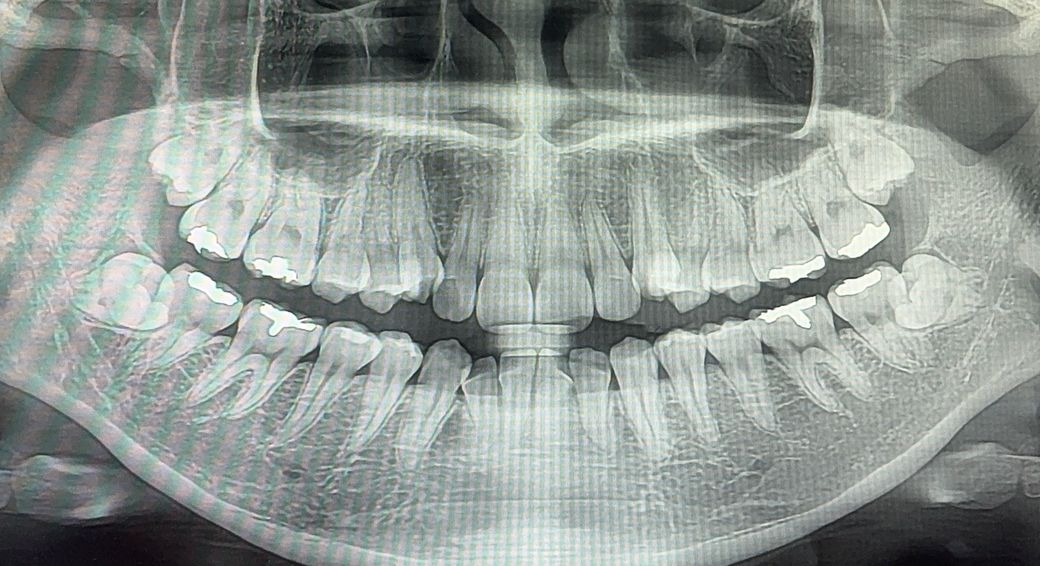

치아 교정 할까 고민 중인데 블랙 트라이앵글이 걱정됩니다

위 송곳니 2개가 덧니라서 송곳니 뒤에 있는 치아를 각각 하나씩 발치하고, 아래는 발치 없이 교정해야 한다고 하셨습니다 (총 발치 2개)

제가 지금도 시린이 완화 치약을 사용하고 있어 걱정되고, 아래 앞니 두개가 완전히 맞닿아 난 상태라 이걸 교정으로 폈을 때 그 사이 블랙 트라이앵글이 심해질까봐 걱정됩니다

• 1번 째 사진